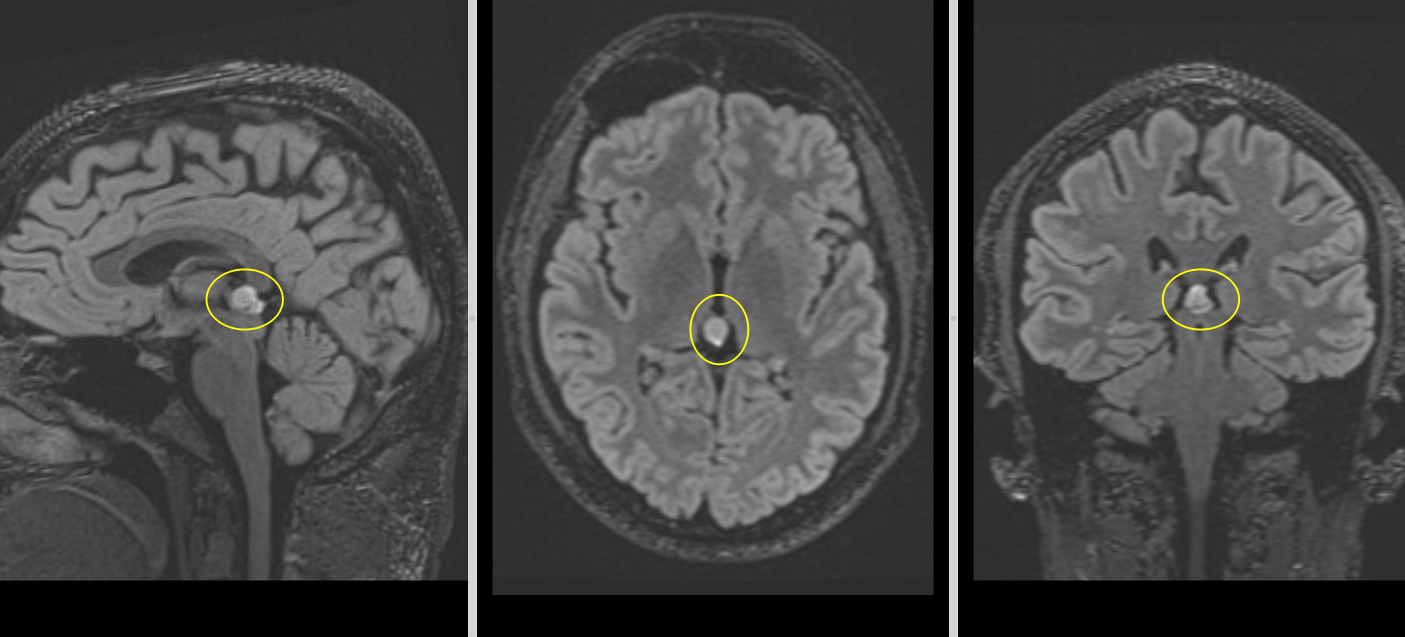

Tumoră de glandă pineală – determinări secundare în pereții ventriculari